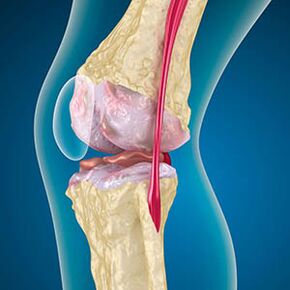

With osteoarthritis, cartilage lining the edges of the bones is abrasion or completely absent.The damaged tissue is not a source of pain because it has no receptors.Inflammation in neighboring structures causes characteristic symptoms.

The body continues the regeneration of damaged tissues, but cartilage is developing unevenly.Consequently, irregularities are formed which hurt other elements of the joint.The nature of the osteophytes is explained by compensation for cartilage smooth articulation.Another version indicates that the growth of "spurs"It is associated with an attempt to stabilize the medial or lateral joint due to muscle weakening.

The osteoarthritis of the knee joint combines two processes: destruction of cartilage and the growth of osteophytes or bone spurs.The process stage is determined by radiography.Rooming osteoarthritis is the destruction of the knee joints with age, the natural process of aging.The causes are a weakening of the muscles and a bad blood supply to the tissues.How to get treatment without surgery?Eliminate the factors that have reduced muscle tone.